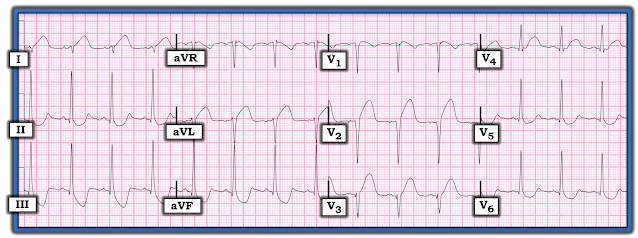

Because of this CT interpretation, they recorded an ECG:

It is clear that this transmural ischemia (STEMI/OMI) could have been diagnosed earlier with an ECG.

The ECG is all but diagnostic of LAD occlusion (Occlusion MI, or OMI)

Interesting case for this unfortunate young man who died from his severe head injury. The initial ECG in today's case (which I have reproduced in Figure-1) is markedly abnormal — with profound, coved ST elevation in not only the anterior leads — but also high lateral leads I and aVL + mirror-image opposite inferior lead ST depression (to the aVL ST elevation) + marked right axis (consistent with LPHB) + and not only loss of anterior R waves, but a fragmented downslope to the S wave in lead V3 (often itself a sign that there has been anterior infarction).

Dr. Smith lists 2 potential reasons to explain these ECG findings: i) Acute LAD occlusion; and, ii) Based on Echo findings — Takotsubo cardiomyopathy.

I would add a 3rd potential contributing factor = severe CNS injury — which is notorious for causing QTc prolongation with often unpredictable ST-T wave abnormalities that often result in “pseudo-infarct” patterns.

Obviously — severe CNS injury is not the only cause of ECG abnormalities in today’s case given marked Spectral CT and Echo abnormalities — but I thought the shape of elevated and depressed ST-T waves on today’s initial ECG to be distinctly unusual in the degree of T wave “fattening” (rounding out) at T wave peak and/or nadir (in those leads where the ST is depressed). I thought at least a portion of the unusual ECG findings in Figure-1 may be attributable to severe CNS injury.

Additional Learning Point:

- CNS catastrophes (ie, stroke, bleed, trauma, tumor, coma, seizure, etc.) — are notorious for sometimes producing bizarre ECG findings (QTc prolongation, marked ST-T wave abnormalities that are impossible to predict, "pseudo-infarct" patterns).

| Figure-1: The initial ECG in today's case — obtained from a young man with severe blunt trauma with severe head injury (See text). |